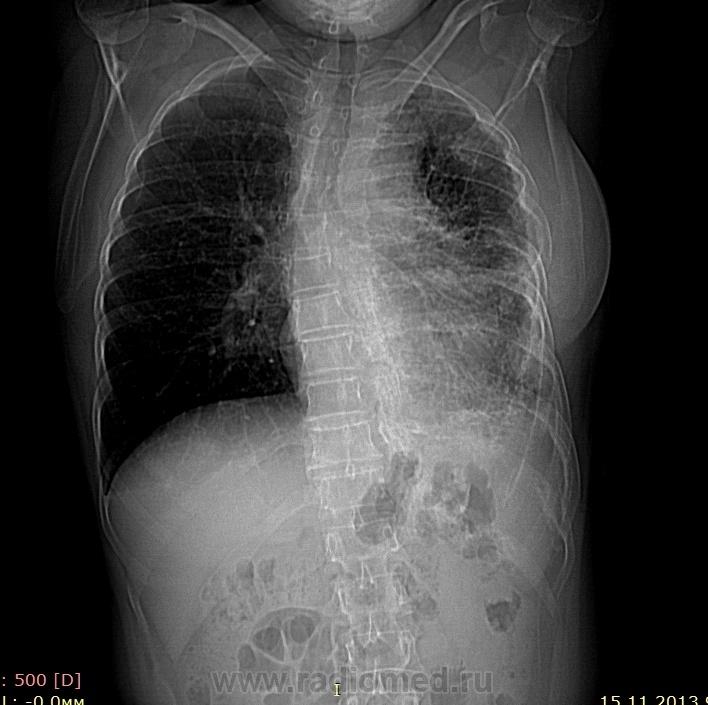

Пациентка 60лет, жалобы на одышку, боли в грудной клетке, слабость( по поведению в кабинете никто слабости не увидел) Из другого района( архива нет), КТ ГМ, легких, шейного отдела позвоночника по "рекомендации платно профессора такого-то". Болеет длительное время( не знаю скоко), обследовалась на ТБ много раз, не выявлено. На онко - " пунктировали, но онкологии не выявили" Т.е. и фтизиатры и онкологи  сказали нет, " а мне болит".

Вот после консультации назначено КТ " черепа, грудной клетки, шейного отдела позвоночника, ОБП".  За голову и позвоночник - в пределах возраста, ОБП на понедельник. А вот легкие непонятны, прошу помочь, может кто сталкивался? Описать-то, описал" как описант", по типу "оссифицирующее диспластическое заболевание легочной и медиастинальной плевры, перикарда, фиброзных оболочек печени и брюшной полости." М.б. кто-то уже видел?

Ничего умного не скажу. Написал бы сочетание "панцирного" сердца и "панцирного" легкого, пневмофиброза.  В кальцификации брюшины не уверен. Бронхоскопию делали?

Хороший вариант - инкрустация плевры как последствие эпмиемы или гемоторакса. Плохой вариант: остеосаркома

по поводу онкологии похоже на симп,том упакованного легкого при мезотелиоме (возможно леченный вариант),а также на леченную лимфому,ну и изменения в ребрах типа 2_ по Людвигу просто поддалкивает на вариант 2

P.P.S. Чем больше смотрю, тем больше тянет на зло, многоузловое поражение плевры, все участки обызвествлений (наверняка это неправильное название) имеют мягкотканный компонент... Так что хороший вариант отметаю.

Как онкорентгенолог остеосаркому отметаю сразу - ни возраст, ни картина, ни анамнез не подтверждают. Можно думать о мезотелиоме, есть варианты с достаточно доброкачественным течением, для них характерны обызвествления, множественность поражения, в точм числе по перикарду, плевре, брюшине. Однако, судя по деформации грудной клетки - процесс очень длительный, все-таки мезотелиома обычно развивается быстрее. Поствоспалительные изменения? Желательно покопаться в анамнезе, было ли какое-то лечение?

Уважаемые коллеги!Боюсь высказать свое мнение,-но складывается впечатление о делах давно минувших дней-больших остаточных изменений п/перенесенного tbc.Не кидайте в меня камнями-я бы не говорила,если бы не видела собственными глазами похожие изменения.

Что до меня, то мне незнакомо ни одно злокачественное поражение плевры, сопровождающееся такими массивными обызвествлениями...

По-моему, просто инкрустация как последствия перенесенного плеврита, скорее всего туберкулезного.

Не узнаем. Пациентку уговорили в НИИ, м.б. для нее лучше. Записи КТ были конс. в ОКБ , заинтересовались ученые и т.д. От нас пациентку забрали. Все ,что успел - выложил. По тел. с ОКБ:  Тб - отрицание полное, болезнь "свежая"( 1-1,5года!), убеждение ученых о мезотелиоме, НО экстраоссальную остеосаркому никто не отверг! Еще какие-то лимфосарко. Короче диагноза нет, по КТ ОБП на словах: "вдоль левого мочеточника до м.таза похожая продольная оссификация с частичным нарушением оттока, участки оссификации передней бр. стенки. Оссификация нескольких лимфоузлов  вдоль аорты."  Вроде на биопсию согласилась, но только не в ЦРБ и не ОКБ, а в НИИ.